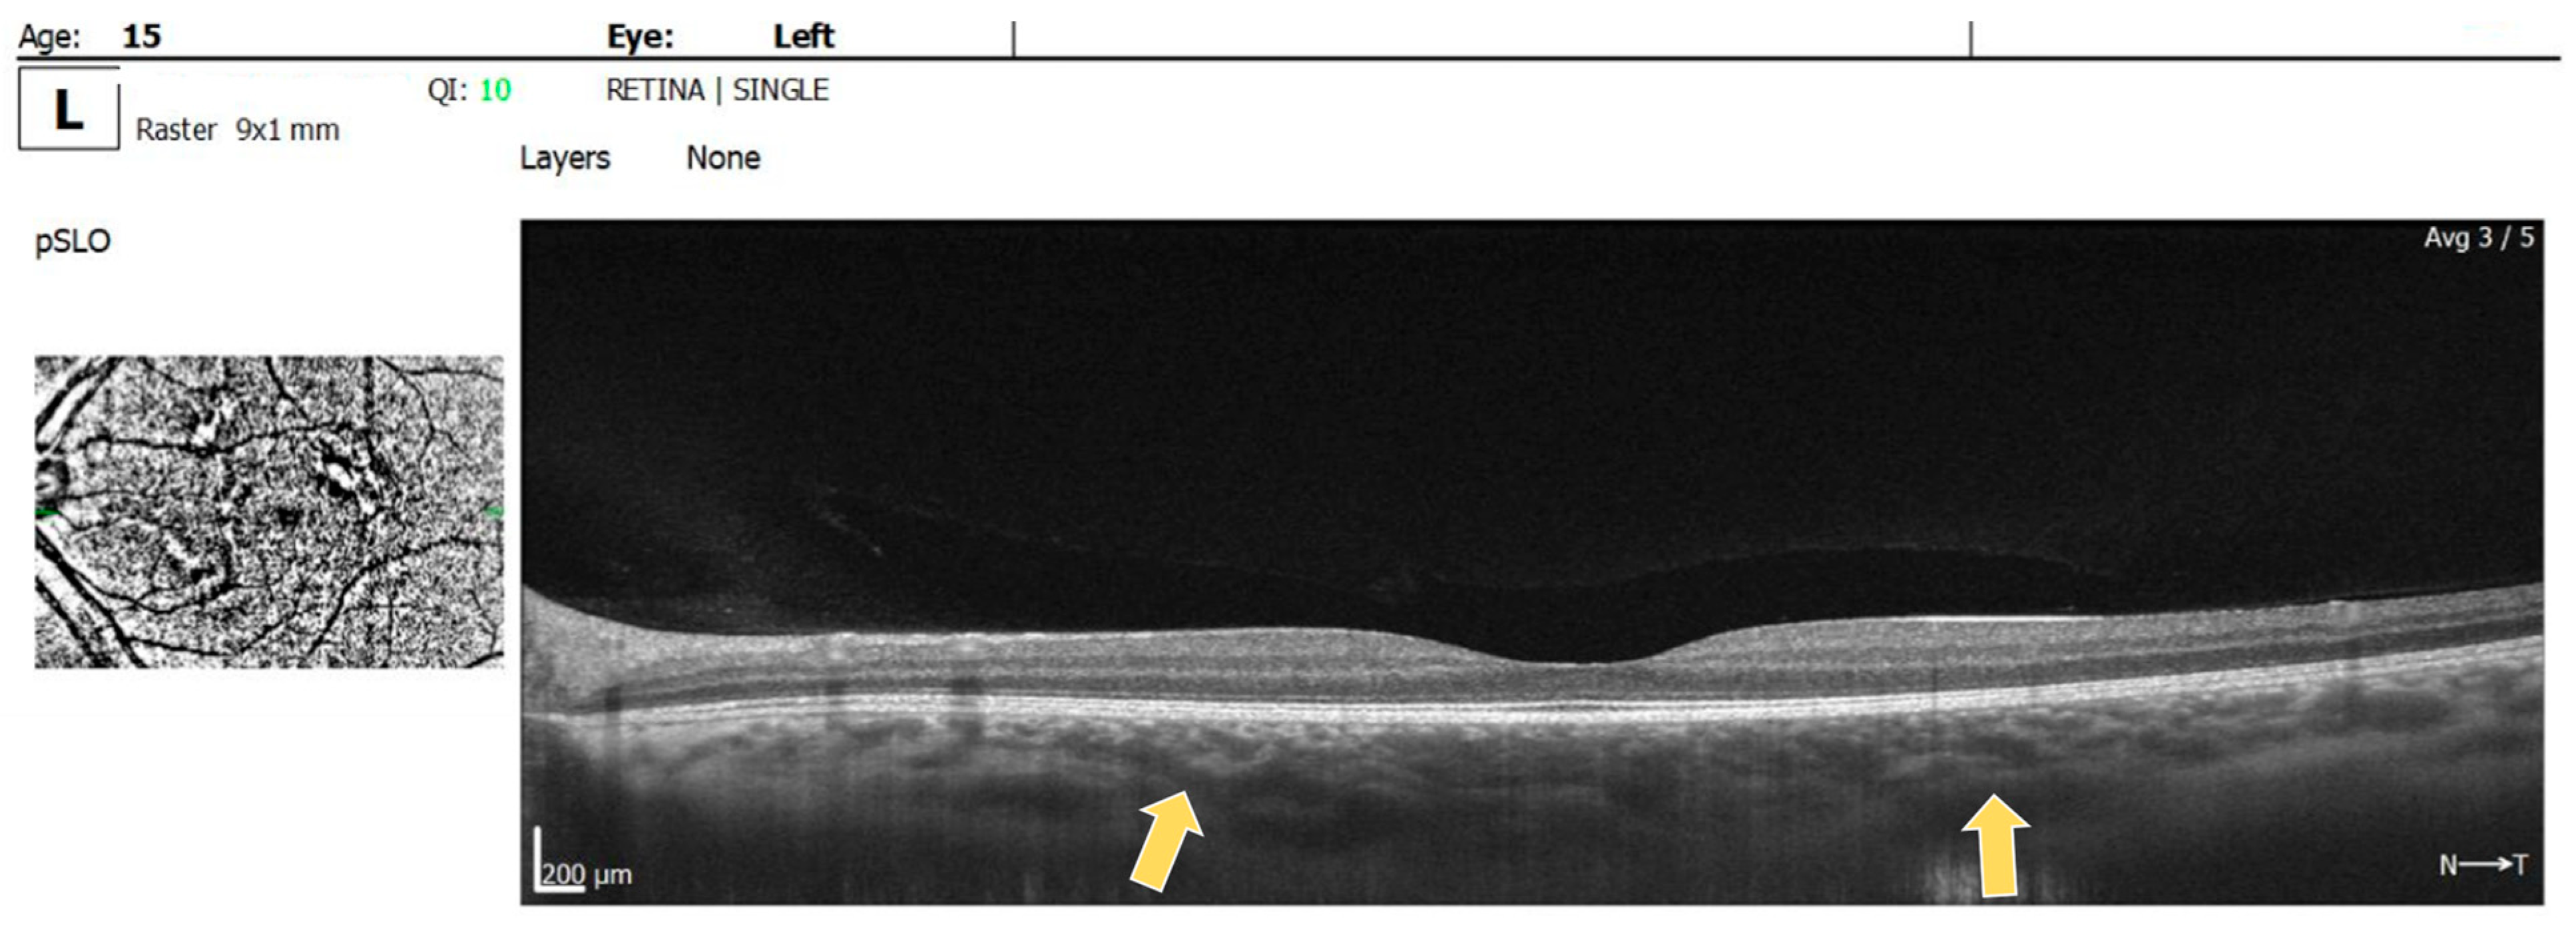

2. Case Report